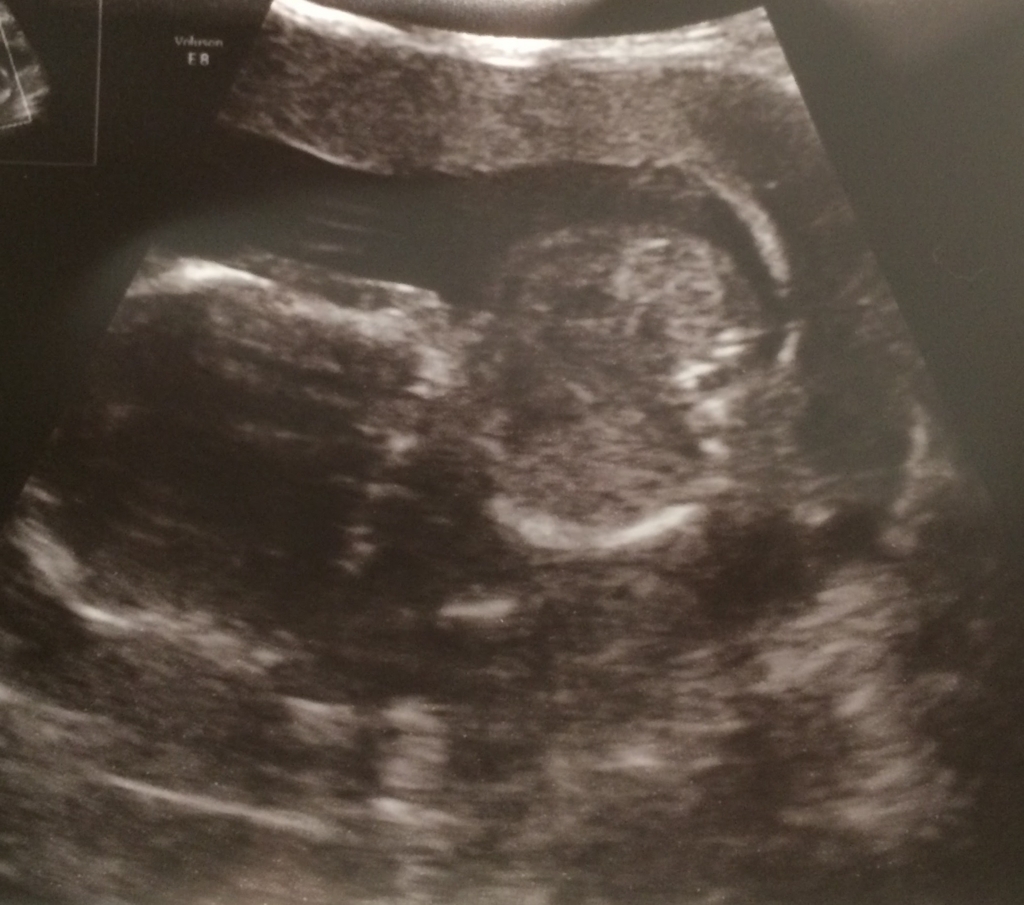

エコー写真ではひと型が見えて興奮しました。